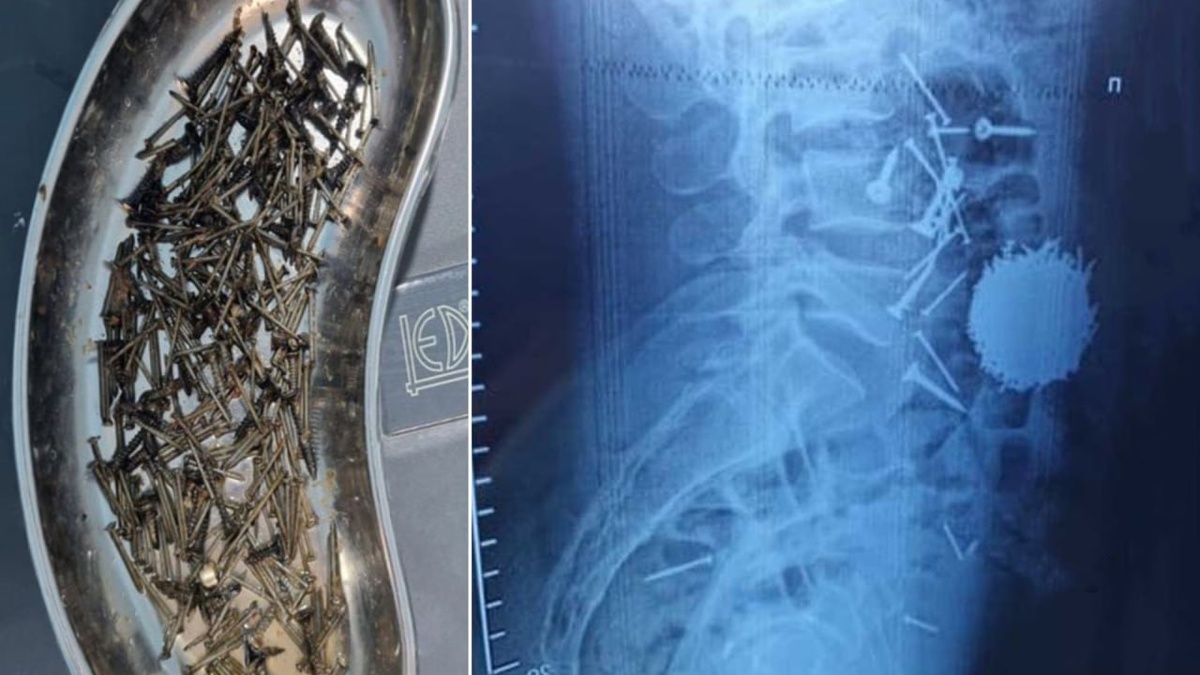

Samarqandda erkak stress sabab 200 grammga yaqin mix va samorezlar yutib yubordi

Respublika shoshilinch tibbiy yordam ilmiy markazi viloyat filialiga 29 yoshli fuqaro qorin sohasidagi kuchli og‘riq bilan murojaat qilgan. @daryolive